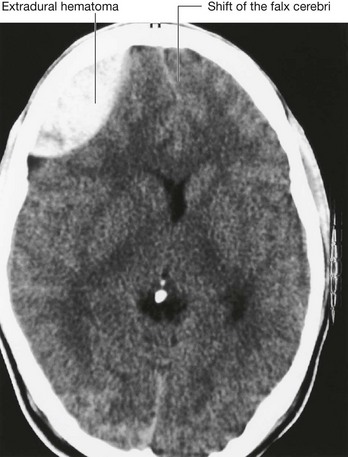

In the clinic

Medical imaging of the head

Radiography

Until two decades ago the standard method of imaging the head was plain radiography. The radiographs are taken in three standard projections—namely the posteroanterior view, the lateral view, and the Towne’s view. Additional views are obtained to assess the foramina at the base of the skull and the facial bones. Currently, skull radiographs are used in cases of trauma, but such use is declining. Skull fractures are relatively easily detected (Fig. 8.28). The patient is assessed and treatment is based upon the underlying neurological or potential neurological complications.

Computed tomography

Since the development of the first computed tomography (CT) scanner, cerebral CT has been the “workhorse” of neuroradiological examination. It is ideally used for head injury because the brain and its coverings can be easily and quickly examined and blood is easily detected. By altering the mathematical algorithm of the data set the bones can also be demonstrated.

Fractures of the skull vault and extradural hematoma

The skull vault is a remarkably strong structure—and quite rightly, because it protects our most vital organ, the brain. The shape of the skull vault is of critical importance and its biomechanics prevent fracture. From a clinical standpoint skull fractures alert clinicians to the nature and force of an injury and potential complications. The fracture itself is usually of little consequence (unlike, say, a fracture of the tibia). Of key importance is the need to minimize the extent of primary brain injury and to treat potential secondary complications, rather than focusing on the skull fracture. Skull fractures that have particular significance include depressed skull fractures, compound fractures, and pterion fractures.

Pterion fractures

The pterion is an important clinical point on the lateral aspect of the skull. To find the precise point of the pterion, an imaginary line 1 inch (2.5 cm) above the zygomatic arch, and 1 inch (2.5 cm) posterior to the lateral orbital margin will approximate to this region. At the pterion the frontal, parietal, greater wing of the sphenoid, and temporal bones come together. Importantly, deep to this structure is the middle meningeal artery. An injury to this point of the skull is extremely serious because damage to this vessel may produce a significant extradural hematoma, which can be fatal.